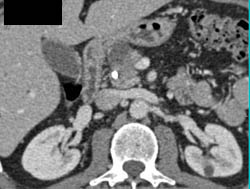

Cystadenoma of the Pancreas